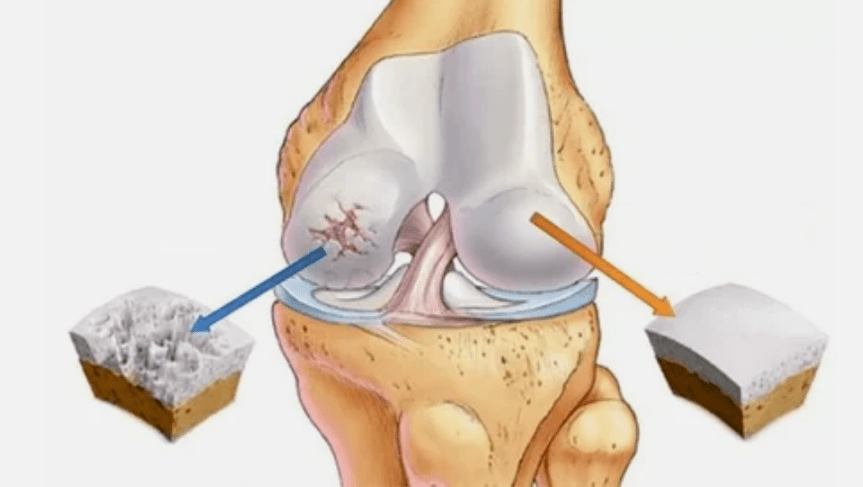

- A lesión primaria afecta á cartilaxe hialina. No caso de trastornos circulatorios, hai un deterioro na forza patolóxica. É o primeiro paso ou a primeira causa de que se poida producir artrose.

- Patoloxías de revestimento de hialina. O adelgazamento da cartilaxe leva á substitución do seu tecido patolóxico - estruturas óseas.

- O crecemento anómico aparece na cartilaxe - osteófitos.

- A violación que se produce da anatomía natural da cartilaxe e os ósos leva á sobrecarga de áreas de cartilaxe saudables. A destrución de tecidos articulares sen tratamento segue liderando e leva a discapacidades.

Se aumenta o grao de enfermidade, os procesos patolóxicos aínda son peores. Ao final, todo o hialink NORP é destruído.